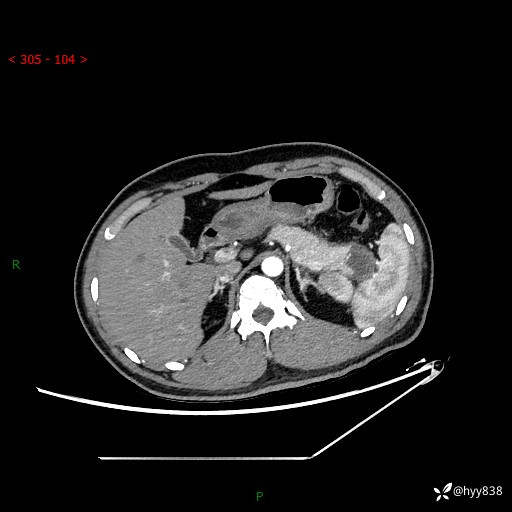

【患者信息】:31岁/男

【主诉】:间断性左下腹疼痛10天

【现病史及既往史】: 患者10余天前无明显诱因出现左下腹部疼痛,呈间断性,无恶心,呕吐,无黄疸,腹泻症状,于当地医院就诊,行腹部C提示:胰腺尾部占位。2型糖尿病。现患者为求手术治疗,门诊以“胰腺肿物”收入院。 患者起病来,一般情况可,大小便正常,体重体力未见明显减轻。

【检查】:胰腺CT平扫+增强